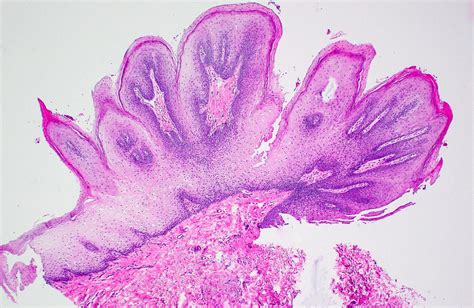

Identifying an Oral Squamous Papilloma often involves observing its distinct morphology. Clinicians look for specific visual cues that differentiate this lesion from other oral pathologies like focal epithelial hyperplasia or squamous cell carcinoma. Because they are exophytic, they grow outward from the surface, often resembling a small cluster of grapes or a delicate cauliflower head.

• Biopsy: The gold standard for diagnosis. A small sample of the tissue is removed and examined under a microscope to confirm the presence of koilocytes—cells characteristic of HPV infection.